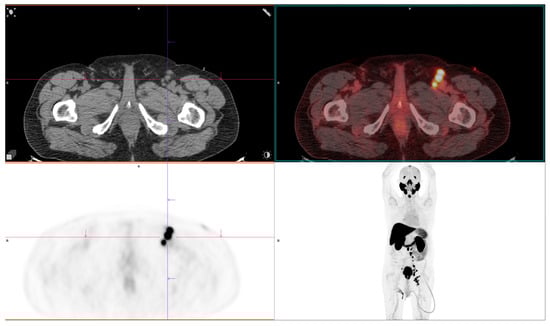

The Role of Nuclear Medicine in Prostate Cancer

Background: Considering the high global frequency of prostate cancer, it is necessary to know the benefits and drawbacks of numerous diagnostic and therapeutic modalities. Methods: In this article, we include 88 manuscripts (46/88 original studies) found on PubMed, written in English in extenso, dealing with nuclear medicine methods in patients with prostate cancer. Results: Choline PET/CT had low sensitivity in detecting the primary tumor. This method has been almost completely replaced by PSMA PET/CT, which is included in international guidelines and recommended for initial staging of unfavorable intermediate- to high-risk prostate cancer, the detection of recurrent disease after treatment, the evaluation of mCRPC, therapy response evaluation, and theranostics. FDG is currently used in aggressive forms of prostate cancer and as a supplement in PSMA PET/CT for patient selection for RLT. Na[18F]F has demonstrated satisfactory diagnostic capacity for evaluating bone loss; however, due to a lack of research, it is not recommended in international guidelines. 18F-Fluciclovine has lower sensitivity than [18F]F-PSMA-1007 for the detection of early biochemical recurrence in prostate cancer. GRPR and SSTR analogs are less frequently used but can be useful in the evaluation of rarer pathohistological types. [99mTc]Tc-PSMA can be used in resource-limited settings where PET/CT is unavailable, with a lower sensitivity compared to [18F]F-PSMA-1007 but a higher sensitivity compared to bone scans. Conclusions: PSMA tracers are important tools for evaluating intermediate- and high-risk prostate cancer, with limitations in 5–10% of prostate cancers that do not express PSMA. Theranostics are increasingly incorporating PSMA. Full article

Show Figures

Figure 1